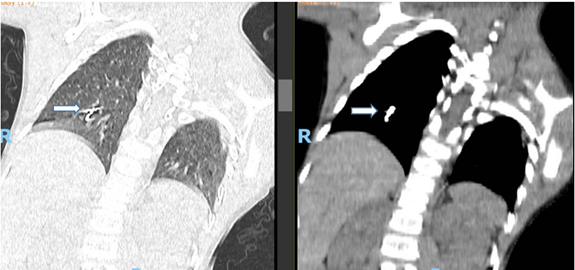

A 6-year-old boy with a known history of cerebral palsy and spastic quadriplegia presented to the emergency department (ED) two hours after inhaling a metallic dental bur during a dental procedure at an outpatient clinic. His initial physical examination was unremarkable. A chest X-ray performed in the ED revealed the FB in the right lower lung zone. A subsequent CT scan confirmed the presence of a 2.5 cm metallic FB lodged within the bronchioles of the right lower lung.

Figure 2a: CT scan chest (horizontal view) showed: Metallic foreign body at the bronchioles of the right lower zone measured 2.5cm.

Figure 2b: Coronal view.